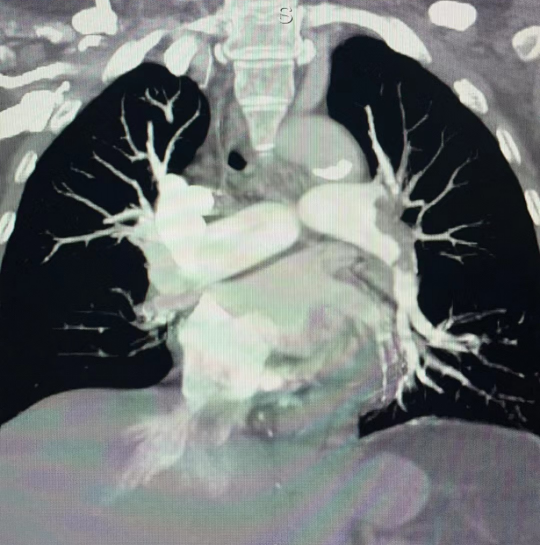

66岁的曹女士,一月前因左脚扭伤至骨折,予以石膏固定,近一月一直在家卧床制动,一天在下床时突发胸闷,憋喘,呼吸困难,伴有濒死感,持续不能缓解。随后来到我院东城院区门诊就诊,心血管内科门诊医师蒋丽根据患者的临床表现及心电图和血气分析结果高度怀疑是急性肺动脉栓塞,完善急诊肺动脉CTA检查后,最终确诊为严重肺动脉栓塞,且血栓巨大,几乎将半个左侧肺动脉以及整个右侧肺动脉完全堵死,临床保守治疗死亡率极高。

取得患者及家属同意后,经过缜密的术前准备,11月6日,在影像中心、介入导管室等多学科密切配合下,张勇带领施益忠、吴浩、祝大明手术团队,成功为患者实施了微创介入手术,手术共用时约90分钟。术中造影见左上肺动脉开口及右侧肺动脉主干巨大血栓影,管腔血流完全堵死。予以血栓机械碎栓+药物靶向溶栓术后,肺动脉血流完全恢复,患者憋闷症状明显好转,术后患者恢复良好,1天后可下床自由活动。日前患者已康复出院,转居家抗凝治疗及门诊随访。